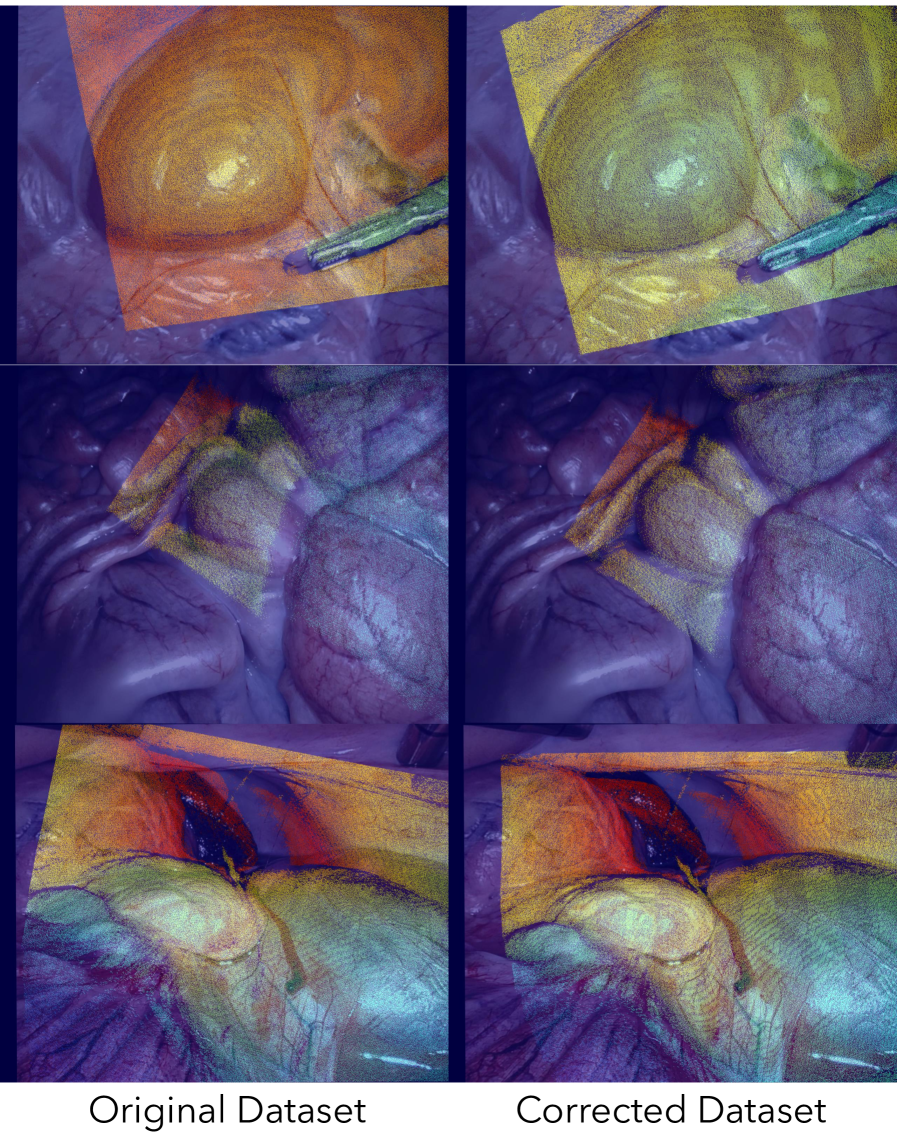

Among these tasks, depth estimation presents unique challenges in the surgical domain. Due to physical constraints of minimally invasive surgery, it is difficult to acquire ground truth depth maps in surgical scenes. The SCARED dataset uses an external structured light sensor in ex vivo porcine tissue. To generate a video dataset with paired depth, the endoscope is moved using the robotic arm and the keyframe depth map is reprojected into the non-keyframe camera views. Due to calibration and kinematics errors, these depth maps are not reliable for training or evaluation, shown in Fig. 10. We use COLMAP (Schönberger and Frahm, 2016) to correct the non-keyframe depth maps; see Appendix D for details. We will release this corrected dataset for public use.

We repeat this process for every video sequence. Fig. 10 displays qualitative results of this correction algorithm. We will release the codebase and corrected dataset to the public upon paper acceptance. Table 4 displays the train-validation split we used to conduct experiments.

Figure 10: Samples of the original SCARED dataset (left column) and COLMAP-corrected SCARED dataset used in this paper (right column). Note that depth maps are better aligned to the RGB image.